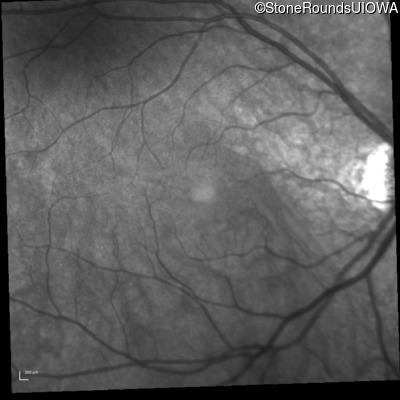

Infrared Fundus Photograph - Right - 20/50 +2

Exemplar